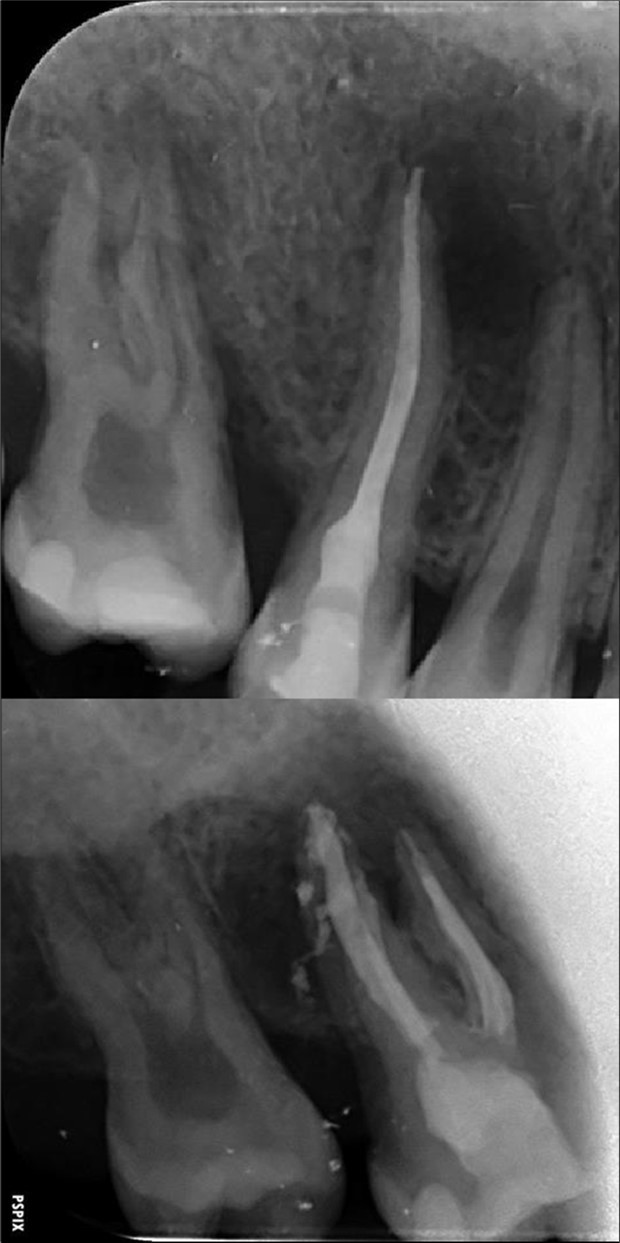

Complete healing of periapical lesions and treatment of teeth 26 and 16 with advanced endo-perio lesions posed challenges due to the patient’s delayed supplementation. In this case, surgical endodontic procedures and the extraction of teeth with advanced endo-perio lesions were considered risky because of the underlying metabolic healing impairment. Figure 3

Figure 3.6. 7, 8, 9, and 10 showing postoperative periapical radiographs of these endodontic treatments.

6. 7, 8, 9, and 10 showing postoperative periapical radiographs of these endodontic treatments.